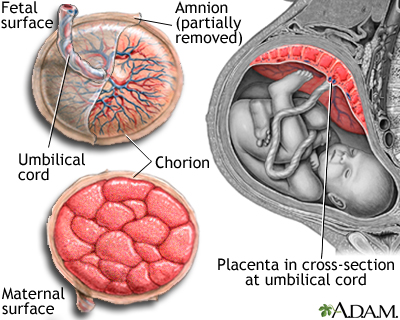

Placenta previa is a problem of pregnancy in which the placenta grows in the lowest part of the womb (uterus) and covers all or part of the opening to the cervix.

The placenta grows during pregnancy and feeds the developing baby. The cervix is the opening to the birth canal.

During pregnancy, the placenta moves as the womb stretches and grows. It is very common for the placenta to be low in the womb in early pregnancy. But as the pregnancy continues, the placenta moves to the top of the womb. By the third trimester, the placenta should be near the top of the womb, so the cervix is open for delivery.